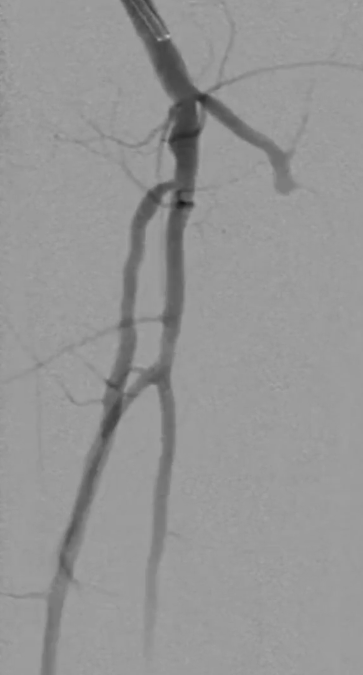

造影显示中段仍有局限性夹层,为保证远期通畅率,植入补救性支架并以5mm球囊后扩张

远端分支处理

造影发现颈前动脉疑似小血栓栓塞,尝试超选后用 3mm 普通球囊扩张,血流恢复(远端膝下三分之二流速尚可),因手术时间及患者配合度限制,未进一步处理。